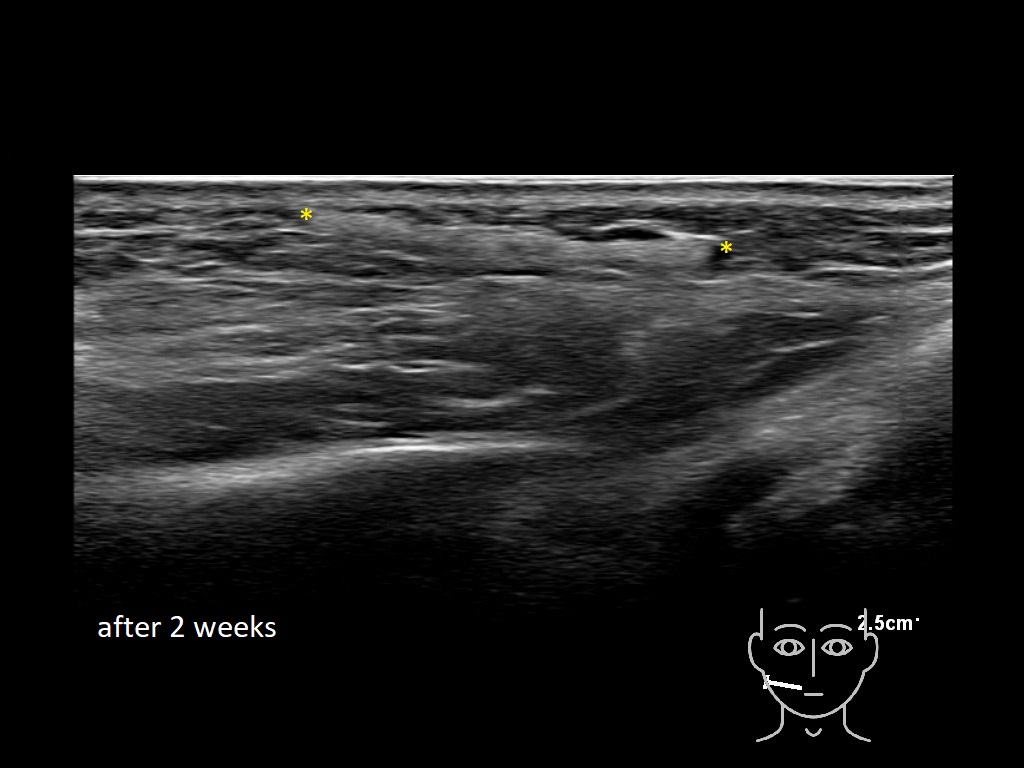

Draw in the image on the right where the fillers are located. To check if your answer is correct, please click on the secondary image.

Draw in the second image below where the fillers are located. To check if your answer is correct, swipe the first image to the right.